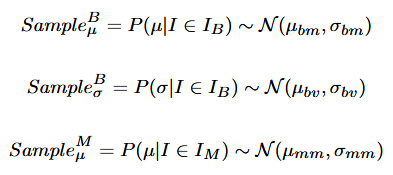

本文中的甲状腺超声图像数据采集自天津医科大学肿瘤医院,包括8232张良性图像(BI,图2©)、9966张恶性图像(MI,图2(d))和404张正常图像(NI,图2(b)),均由专业影像医师标注。

我们将数据集划分为不同子集以训练和测试 PTGAN 及分类器,如图5(a)所示。

PTGAN的训练集包含4000张BI、6000张MI,验证集包含2000张BI、2000张MI。

我们选择VGG-19[37]作为辅助诊断模型。在正常-疾病实验中,我们将285张NI、1932张BI和1666张MI作为训练集,119张NI、300张BI和300张MI作为测试集,如图5(b)所示。

由于良性和恶性数据之间不存在不平衡,我们随机选取特定类别的部分数据人为制造不平衡情况,如图5(b)所示。

首先,部分BI(700训练,300测试)和MI(3666训练,300测试)被作为数据集之一用于辅助诊断模型。

其次,部分MI(800训练,300测试)和BI(3932训练,300测试)被作为另一个不平衡数据集。

最后,生成的数据分别加入训练集,如图5(b)中的虚线框所示。

我们使用生成数据将训练集平衡至接近的数量,如图5(b)所示。